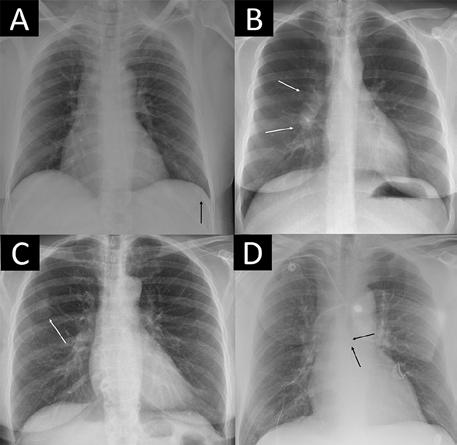

Figura 3. Cuatro ejemplos de radiografías de tórax notables con hallazgos críticos no detectados. La herramienta de inteligencia artificial (IA) fue posprocesada por el proveedor de IA escalando cada una de las 85 predicciones individuales notables a un valor normalizado y utilizando el nivel de caso más alto de las puntuaciones escaladas como la puntuación de probabilidad general de 0 a 1 para "notable" (es decir, la probabilidad de hallazgos anormales o notables por la IA). (A) La radiografía de tórax en una paciente de 49 años muestra una fractura de costilla aguda ligeramente visible (flecha) que la IA no detectó en todos los umbrales y que tampoco detectó el informe radiológico. (B) La radiografía de tórax en una paciente de 30 años muestra ganglios linfáticos hiliares agrandados (flechas) que no detectó el informe radiológico pero no la IA en ningún umbral. (C) La radiografía de tórax de una paciente de 67 años muestra un tumor que imita una placa pleural (flecha) que se informó en el informe radiológico (donde la paciente fue derivada para una TC) y que la IA no detectó en el umbral del 98,0 %, pero no en los umbrales del 99,0 % y el 99,9 %. (D) La radiografía de tórax de un paciente masculino de 64 años muestra un catéter venoso central que posiblemente ingresa en la vena ácigos (flechas), que se clasificó como normal en el informe radiológico. La IA no detectó el hallazgo crítico en el umbral del 98,0 %, pero no en los umbrales del 99,0 % y el 99,9 %.